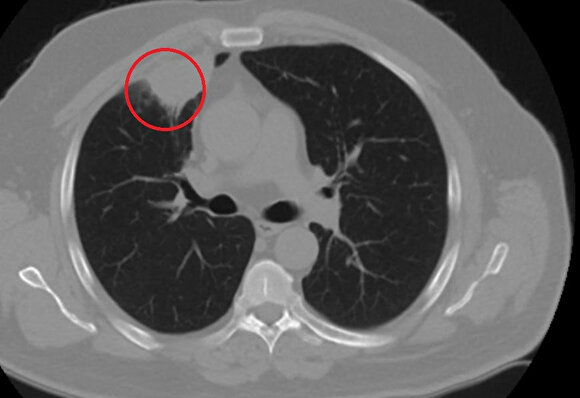

Kent dışında çalışan N.T.'nin, göğüs ağrısı şikayetiyle gittiği hastanede çekilen tomografisinde sağ akciğerinde 4 santimetre çapında tümör tespit edildi. Kanser olabileceği şüphesiyle yapılan ileri tetkikler sonrası N. T.'ye akciğer kanseri teşhisi kondu ve acil ameliyat kararı verildi.

Ameliyat öncesi N.T.'nin Covid-19 testi pozitif çıkınca operasyon ertelendi. Koronavirüs tedavisine başlanan N.T.'nin son testi negatif çıktı. Dr. Fatoş Kozanlı, tedavi sonrası tomografisi çekilen N.T.'nin akciğerindeki tümörün yok olduğunu gördü. Kozanlı, N.T.'nin kendilerine başvurduğunda koronavirüs belirtisi olmadığını ancak ameliyat öncesi PCR testi yaptıklarını söyledi. Koronavirüs tedavisinin ardından ortaya çıkan sonucun kendisini de şaşırttığını belirten Kozanlı, şunları söyledi:

"Hastamız, çalıştığı başka bir kentte göğsünden darbe alıyor ve ağrıları geçmeyince bir üniversite hastanesine başvuruyor. Burada hastaya bir akciğer grafisi çekiliyor. Sağ akciğerinde bir kitleye rastlanıyor. Daha sonra hastaya, bir akciğer tomografisi çekiliyor ve göğüs cerrahisi için önemli büyüklükte olan 4 santimetre çapında, akciğer kanserine benzer özellikte radyolojik bulgular olan bir kitle tespit ediliyor. Daha sonra hastaya yapılan ileri tetkiklerde akciğer kanseri teşhisi konuluyor. Hastaya bir cerrahi planlanıyor. Hasta Kahramanmaraşlı olduğu için kendi memleketine gelmeyi tercih ediyor. Bize başvurdu ve göğüs ağrısı şikayeti vardı. Öksürük, nefes darlığı, balgam çıkarma, ateş gibi şikayetleri yoktu. Hastayı biz de değerlendirdik ve ameliyat olmasına karar verdik. Çünkü akciğer kanserine çok benzer radyolojik bulguları vardı. Sağlık Bakanlığımızın kuralları gereği her hastayı ameliyat öncesi PCR testi yapılır. Biz de ameliyat gecesi hastadan PCR testi aldık ve testi pozitif geldi. Ameliyatımızı 14 gün erteledik ve hastamıza koronavirüs tedavisi uygulandı. Hasta 14'üncü gün tekrar bize başvurdu ve yapılan PCR testi negatif çıktı. Yeni bir tomografi çektik ve tümörün tamamen ortadan kalktığını gördük. Şimdi sonuç bilgilerinden başlangıca gittiğimizde, bu bir akciğer kanseri olsaydı, ortadan kalkması mümkün değildi. Başka bir patolojiye bağlı durum olsaydı, yine verdiğimiz tedaviyle ortadan kalkmasını çok beklemeyiz. Antiviral tedavisi verdik ve hastanın radyolojik bulguları neredeyse tamamen normale döndü. Hastaya bunu izah ettik, 'Dünya literatüründe hiç görülmeyen bir radyolojik bulgu' diyerek. Bu gördüğümüz manzara artık hastanın akciğer grafisinde yok, akciğer kanseri değil. "